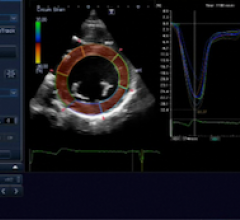

October 14, 2011 — The American Society of Echocardiography (ASE) is preparing a guideline document on using strain ...

October 7, 2011 — There is good news for cancer patients whose medical treatments put them at risk for future cardiac ...